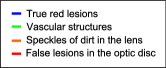

Figure 5 presents a random sample of the potential lesions retrieved by the method on a randomly selected image from DIARETDB1 training set. It is possible to see that most of false positive samples correspond to vascular branching or crossing points, vessel segments and beadings, scars due to laser photocoagulation or black spots of dirt in the capture device, as reported by Seoud et al. (2016). This setting underlines the importance of refine the candidates to remove false positives.

Detailed regions of the embeddings are depicted in Figure 15. This allows better visualization of particular scenarios such as the patches around the true red lesions, the false positive candidates located in the vascular structures, the artifacts due to speckles of dirt in the lens–which are typical of the images in DIARETDB1–and the false detections within the optic disc. In general, it is possible to observe that CNN features are able to better characterize the orientation and the visual appearance of the true lesion candidates, while the hand crafted features can detect the less obvious lesions under low contrast conditions. The ability of the CNN features to discriminate orientations are more evident when dealing with vascular structures. The hand crafted approach, by contrast, is only able to capture the overall size of the vessels and their intensity properties. When combining both strategies, the main advantages of each of them are maintained. The robustness against artifacts is evident for both the deep learning based and the hand crafted features, as these false positive candidates are grouped together into separate clusters from the true lesions. A similar behavior is observed when dealing with false candidates within the optic disc area.